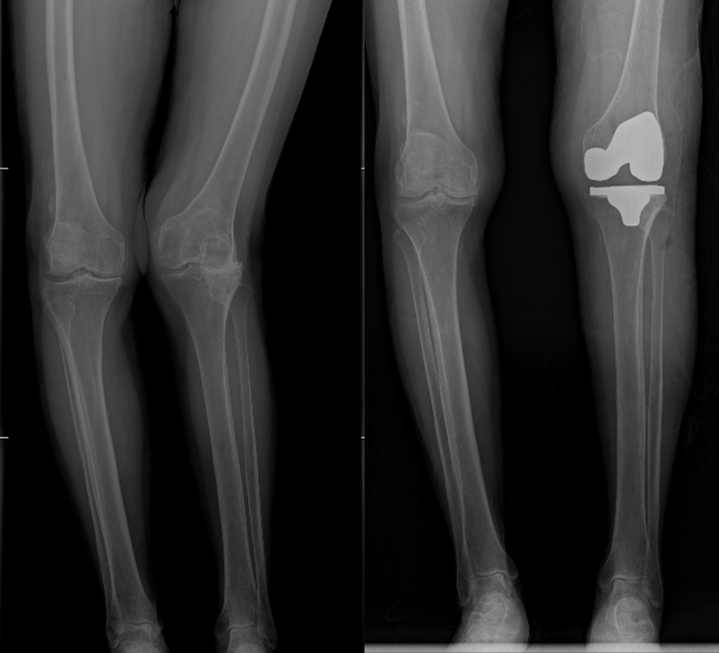

南京鼓楼医院运动医学与成人重建外科在关节治疗领域处于国内领先水平。面对张女士超高龄、复杂关节病变等挑战,王渭君主任团队决定采用Mako机器人辅助关节置换术。这一“黑科技”是该科室的一项先进技术,已成功完成数百例复杂关节置换手术,通过三维建模精准规划假体植入位置,误差控制在毫米级,不仅大幅降低手术创伤,还能根据患者骨骼形态实现个性化治疗。“就像为张奶奶量身定制了一套关节修复方案。这种手术方式可以最大程度地恢复患者关节功能,减少术后疼痛和恢复时间,让患者更快地回归正常生活。”王渭君主任向记者介绍说。

手术当日,在Mako机器人的精准辅助下,团队仅用1个多小时便完成关节置换。术后第二天,张女士就能在助行器辅助下站立行走,“感觉马上就要回到年轻时在球场上奔跑的日子了!”老人激动地说。全程陪护母亲治疗的台湾女儿,被大陆医疗的硬核实力彻底折服。从入院时的智能诊断、手术中的机器人精准操作,到术后多学科协作的康复方案,每个细节都让她惊叹:“原来祖国大陆的医疗技术已经这么先进!” 目睹母亲快速康复,饱受关节疼痛困扰的她当即决定留在南京鼓楼医院江北院区,由王渭君主任团队为自己进行关节治疗。“有这样专业的团队和前沿技术,我对康复充满信心!”